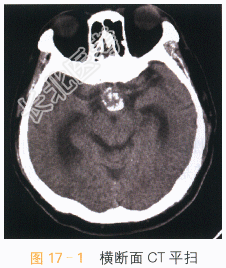

读片分析:头颅CT平扫见鞍上异常软组织影,并可见多发钙化,局部见“蛋壳样钙化”,横断面T₁W见鞍上异常软组织信号灶,呈等高信号影,T₂WI见病灶表现为囊实性肿块;增强扫描实性部分可见明显强化,囊性部分未见明显强化,但正常垂体结构能显示。结合患者临床,可考虑颅咽管瘤。